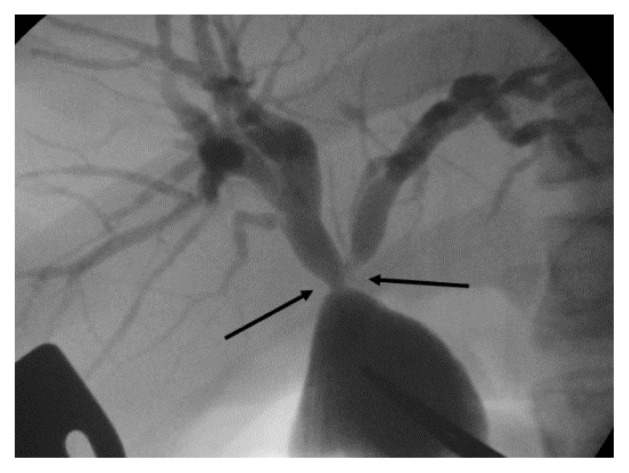

Another patient with Todani IV-A disease underwent radical surgery at 2 years of age. After the surgery, repeated recurrence of cholangitis was observed and treated with antibiotics in each instance. The condition persisted for 10 years. Subsequently, hilar hepatic duct stenosis was detected by DIC-CT. Therefore, hepatic ductoplasty and re-anastomosis were performed when the patient was 12 years old (Figure 3). The cholangitis resolved after the operation, and blood test results were normal. The patient has since recovered, and cholangitis has not recurred as of the most recent follow-up.